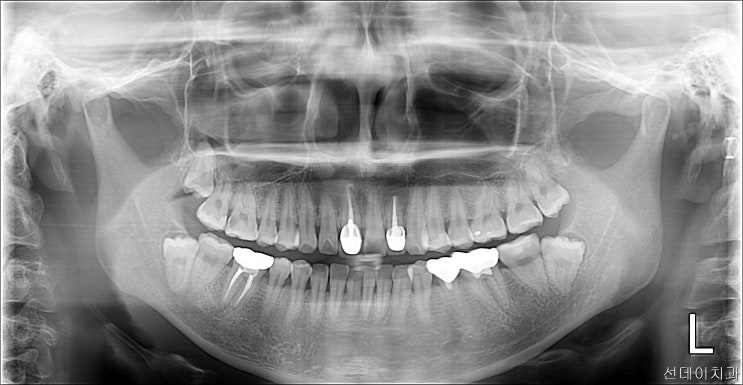

사랑니 뽑지 않아도 되는 관리 방법 알려드립니다!